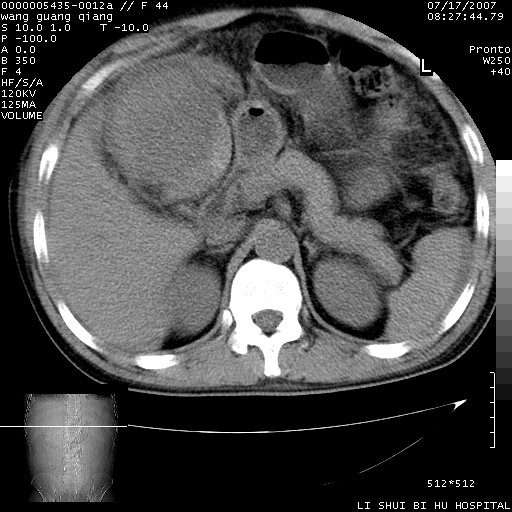

以下是引用dyqct在2007-7-18 10:46:00的发言:[br]胆囊明显增大,壁增厚,明显强化;后下方见大片高密度区,ct值68hu,无强化,周围见多数条纹状高密度影,边界不清。双膈下间隙、肝肾隐窝见带状及片状低密度区。[br]右侧胸壁后缘亦见新月形水样密度区。[br]考虑:1、急性胆囊炎伴周围出血;[br] 2、少量腹水、右侧少量胸腔积液。[br][br][本贴已被 dyqct 于 2007-7-18 10:48:47 修改过]